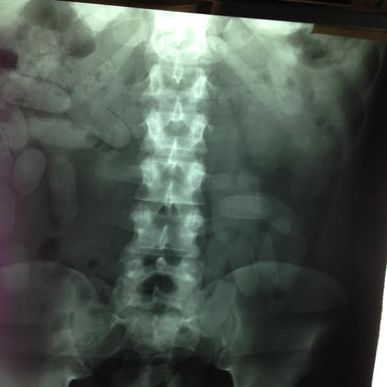

The PCD says they detected the man, travelling with a female companion (also an Italian national), displaying a suspicious behaviour. Both were taken to the San Rafael hospital in Alajuela for a medical examination and x-rays.

Authorities said they found Manzini had swallowed 101 ovules, weighing the equivalent of approximately 432 grams of cocaine.